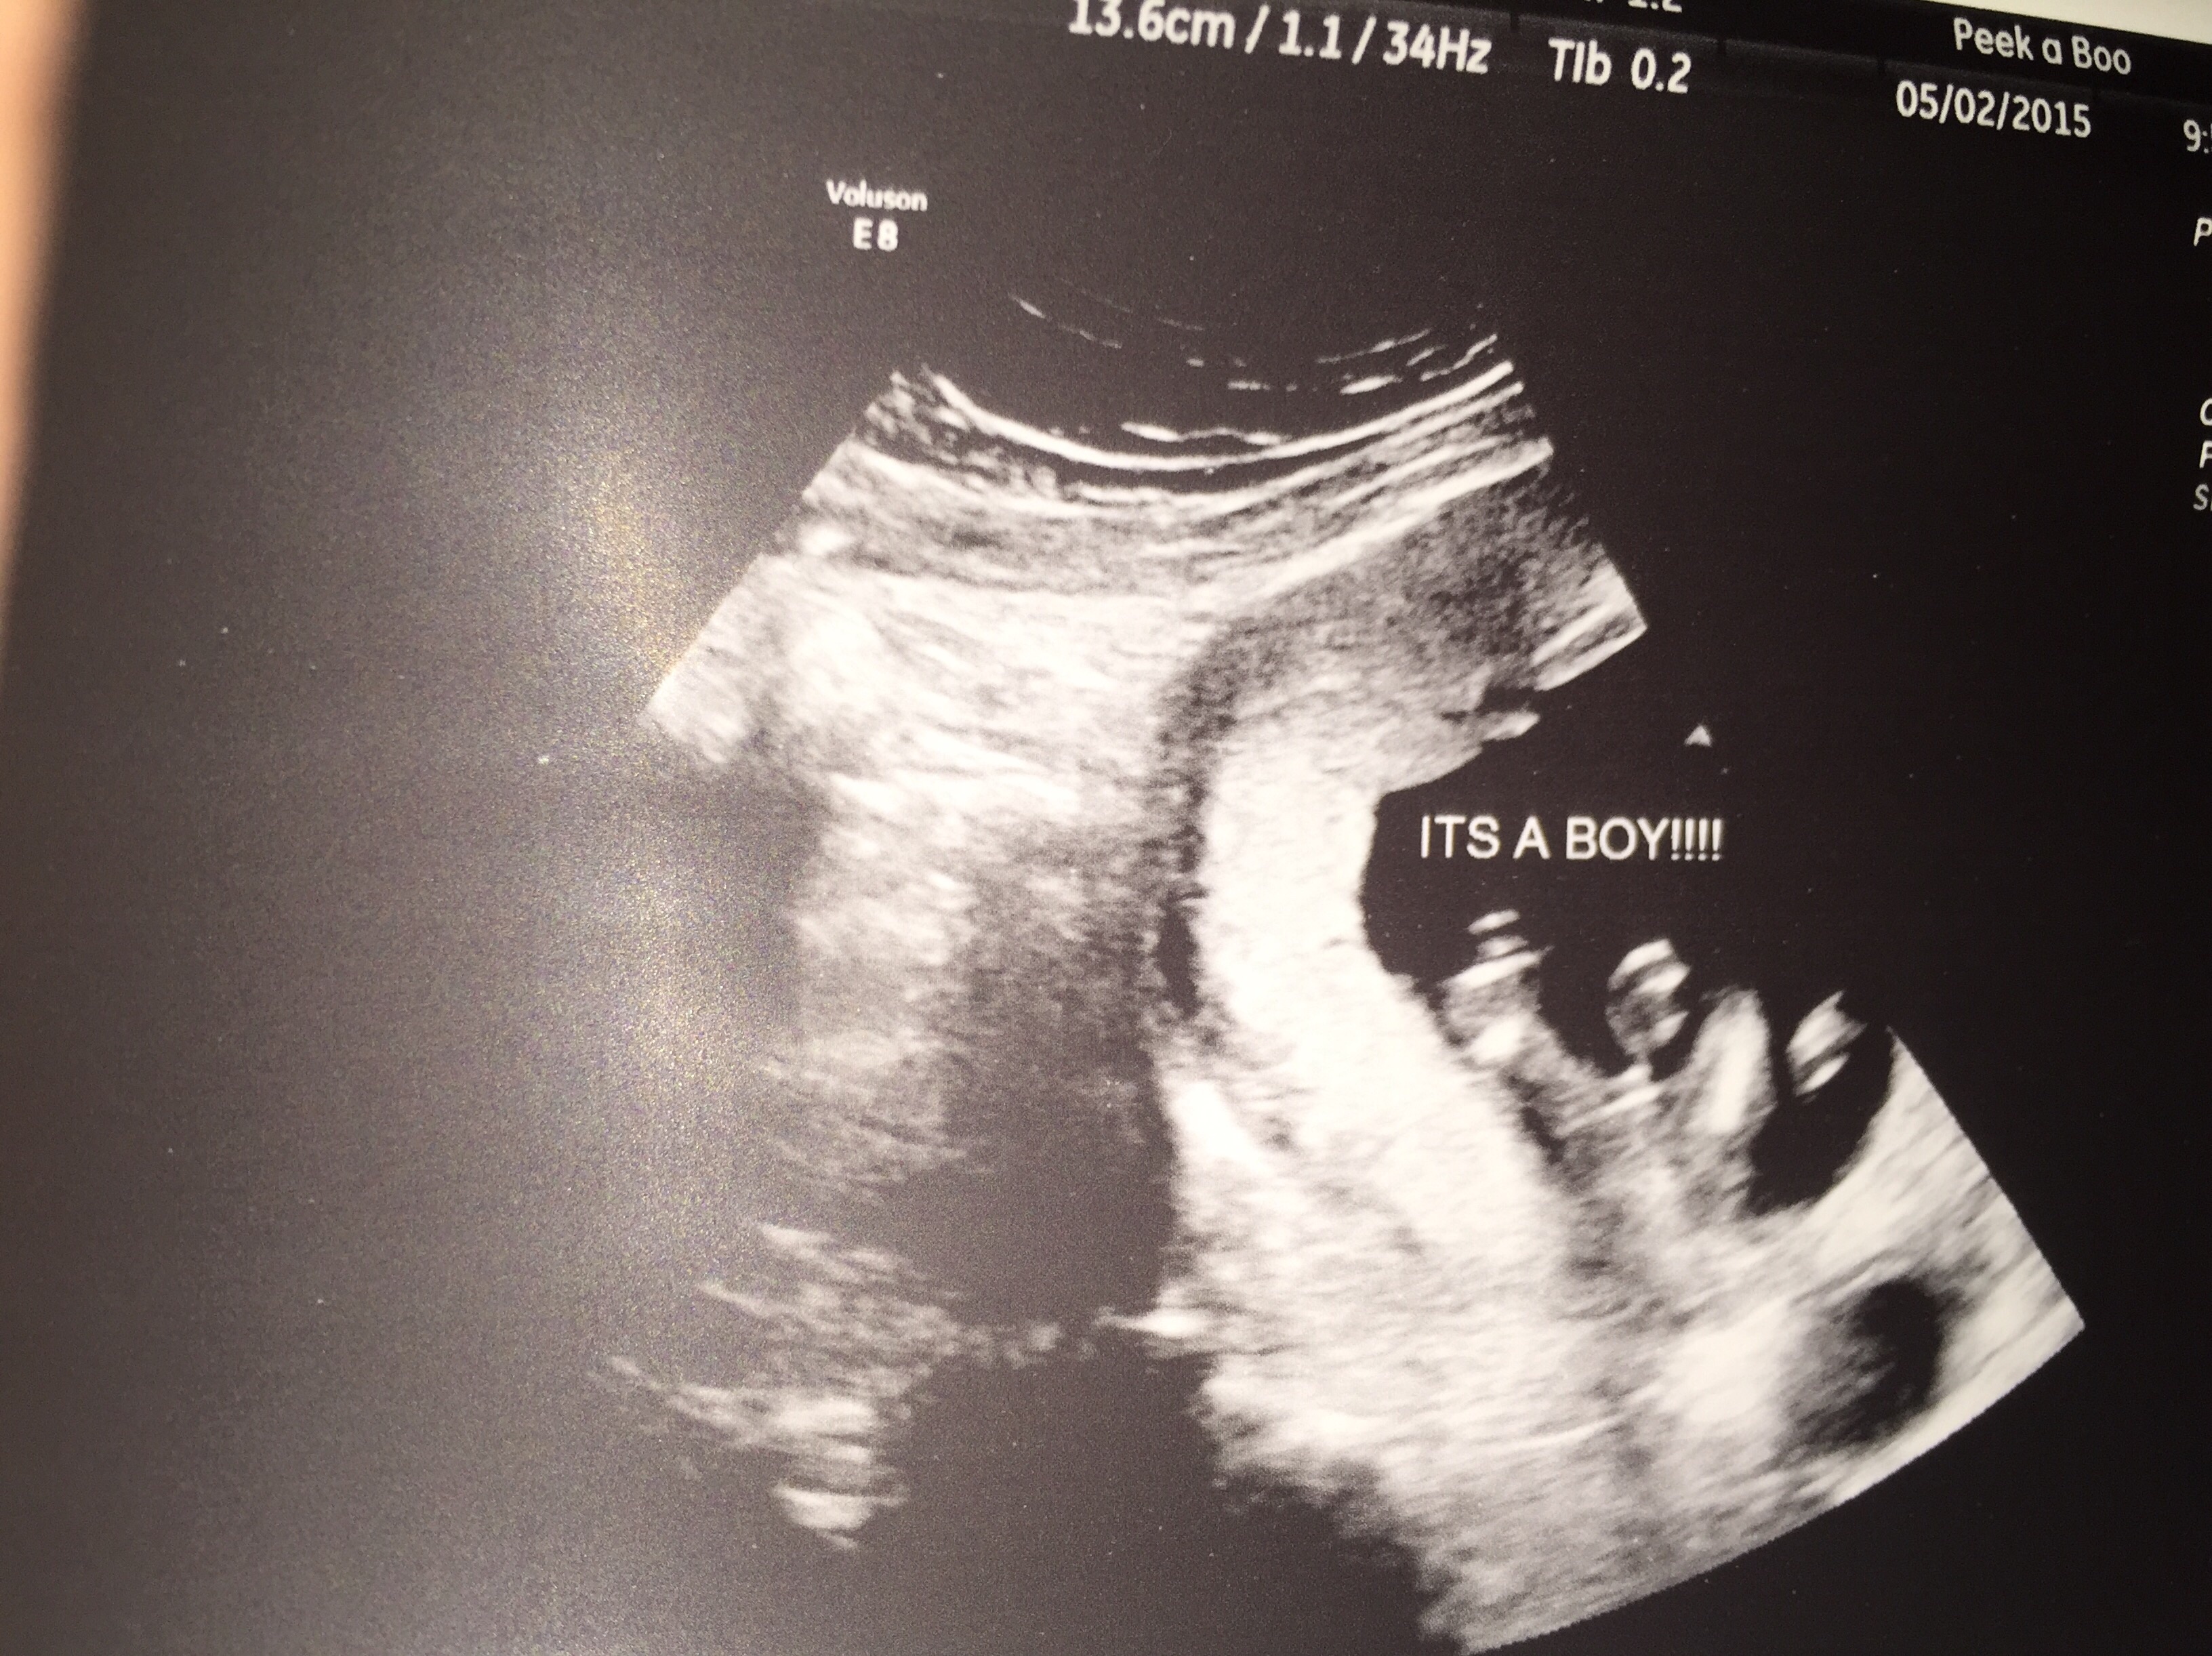

It's a Boy

He wouldn't stop sucking his thumb. It was so cute.